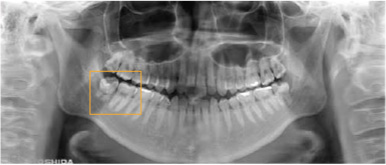

当診療所では、歯科用3Dパノラマ撮影装置(エクセラスマート F+)を導入しております。

これまで以上に、より正確に患部の状態を把握できるようになり、患者様に精度の高い、安全で確実な歯科診療を提供することができるようになりました。

①高画質

従来に比べ、より高画質で高精度の画像撮影が可能に。

歯根の形態から上顎洞・顎関節等に至るまで、総合的により細部の把握が可能になり、1枚の写真で的確な診断が容易にできるようになりました。

小型:最小80μmの

ボクセルサイズを実現

歯根の形態や根尖方向などの

細部の撮影~把握が可能です。